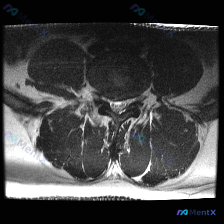

刚整理了一份腰椎MRI读片病例,只有单张轴位T2加权图像,把完整的分析思路整理出来和大家分享。 一、影像基本信息 这是一张腰椎MRI轴位T2加权图像,清晰度良好,解剖结构辨识度高: - 扫描水平为腰椎单个节段(大概率L4/5或L5/S1,具体需结合矢状位确认) - T2序列特征符合典型表现:脑脊液高...

看到这张腰椎MRI轴位的椎间盘病例,整理了完整的读片和分析思路,和大家一起讨论。 一、病例影像基本信息 这是腰椎MRI T2序列的轴位影像,层面位于下腰椎水平,可清晰显示椎体、椎间盘、椎管及周围软组织结构: 1. 核心异常信号:椎间盘髓核信号明显减低,呈中等偏低信号,不符合正常髓核的高信号表现,提示...

整理了一份腰椎MRI读片讨论,给大家分享一下思路。 病例影像基础信息 本次仅提供放射影像-腰椎MRI-T2序列-轴位单张图像,扫描层面为腰椎某一节段,视觉判断符合腰4/5或腰5/骶1椎间盘水平,无临床病史、体征及其他检查资料,核心问题是明确该层面是否存在椎间盘病变相关影像学表现。 影像具体读片结果...

刚整理完一份腰椎MRI轴位片的读片分析,针对椎间盘病变的问题把完整思路梳理出来,和大家一起讨论。 病例影像基础信息 这是一份腰椎MRI T2序列轴位图像,临床问题是评估椎间盘病变,以下是影像可见的核心表现: 1. 椎间盘:该节段髓核T2信号明显减低,呈均匀低信号,也就是我们常说的「黑间盘」,提示椎间...

看到这一份腰椎MRI读片病例,临床怀疑存在椎间盘病变,我们整理一下影像资料和完整分析思路,大家一起讨论。 病例影像资料 本次提供的是腰椎MRI T2序列轴位图像,分析如下: 1. 扫描层面:位于下腰椎节段,可清晰辨认中央的硬膜囊、马尾神经根,以及侧方的关节突关节、椎旁肌肉 2. 核心影像发现: -...